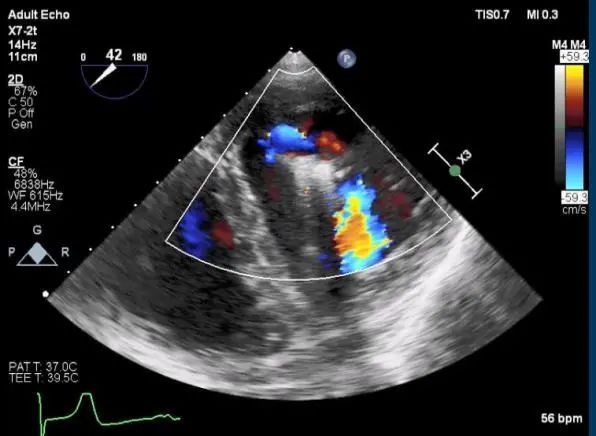

TEE短轴脱垂区域显示(color,血流来源于P2、P3区)

患者麻醉方式同样采取全麻,建立静脉通路后,穿刺右侧股静脉后,预埋ProGlide缝合器后,送导管至房间隔部位,成功穿刺房间隔后进入左房,调整导管角度,顺利到达二尖瓣目标位置,后在X线及食道超声联合辅助下,宋光远教授使用2枚XTR二尖瓣夹,在精确定位后,准确夹合二尖瓣A2-P2以及A3-P3区域,患者收缩压即刻上升30mmHg,左心房收缩压由62mmHg下降至28mmHg,术中测反流面积明显减少,肺静脉多普勒波形由反向恢复正常。手术顺利结束,术后患者即刻苏醒,安返病房。

第二枚XTR夹子释放,返流明显减少

三维超声心动图显示第二枚XTR夹子释放

术后肺静脉频谱

二尖瓣瓣口面积及平均跨瓣压差评估(5mmHg)